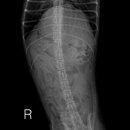

• 24시 에피소드 동물 메디컬 센터 | 만촌동 동물병원 강아지 요골·척골 골절 수술 후기 [24시에피소드동물메디컬센터]

만촌동 동물병원 강아지 요골·척골 골절 수술 후기 [24시에피소드동물메디컬센터] 만촌동 동물병원 ​ 안녕하세요. ​ 풍부한 경험과 따듯한 진료를 바탕으로, 반려동물의 건강하고 행복한 하루하루를 함께 만들어 가는 만촌동 동물병원 24시에피소드동물메디컬센터 입니다. 24시에피소드동물메디컬센터 대구광역시 동구...

에피소드동물메디컬센터(2025-06-26 12:41:00)